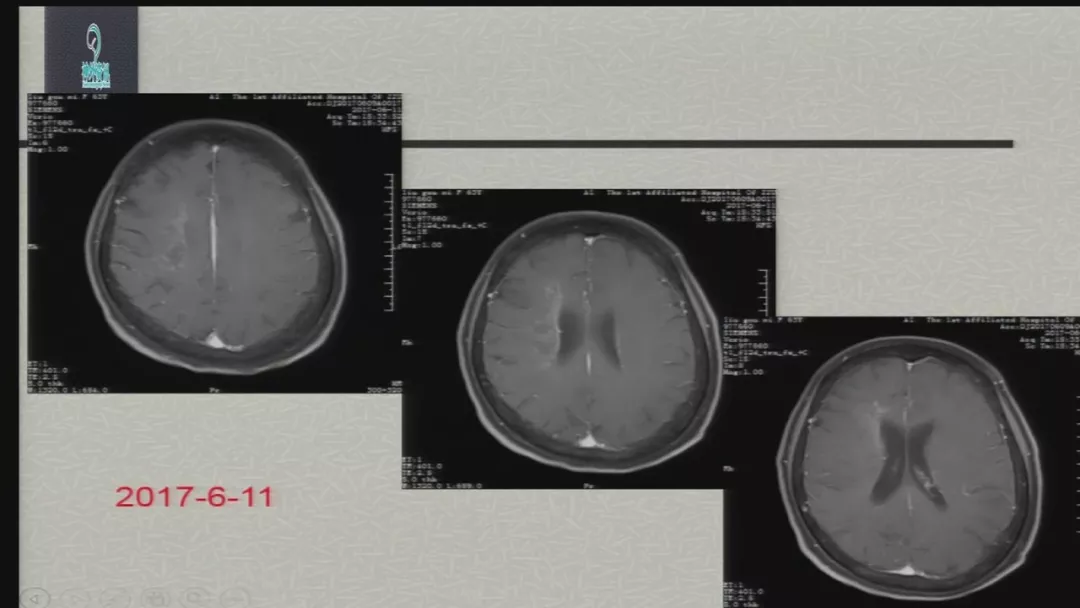

今天为大家分享的是由郑大一附院徐浩文教授在第七届全国介入医学工程大会上带来的“Neuroform EZ在ICAD治疗中的应用”精彩讲课视频和PPT,欢迎观看!(内容未经讲者审核,不当之处请与我们联系)